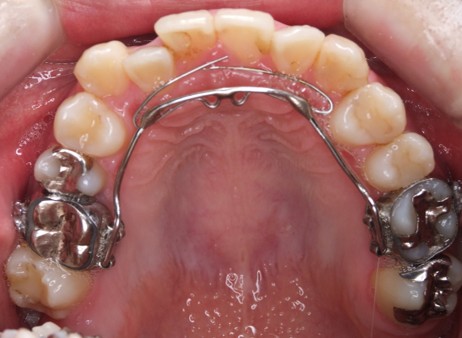

| 主訴 | 50代女性 以前いれた入れ歯が合わなくて使っていないので、しっかり噛めるようになりたい |

| 治療内容 | 矯正治療、インプラント治療、セラミック治療、金属床(部分入れ歯)を行いました。 |

| 治療費 | 4,200,000円(税込み) |

| 治療期間 | 2年(矯正治療期間 1年) |

| 治療回数 | 50回 |

| 想定されたリスク | 重度の歯周病で臼歯部の歯槽骨がかなり吸収していたため、インプラントが脱落するリスクがありました。 |